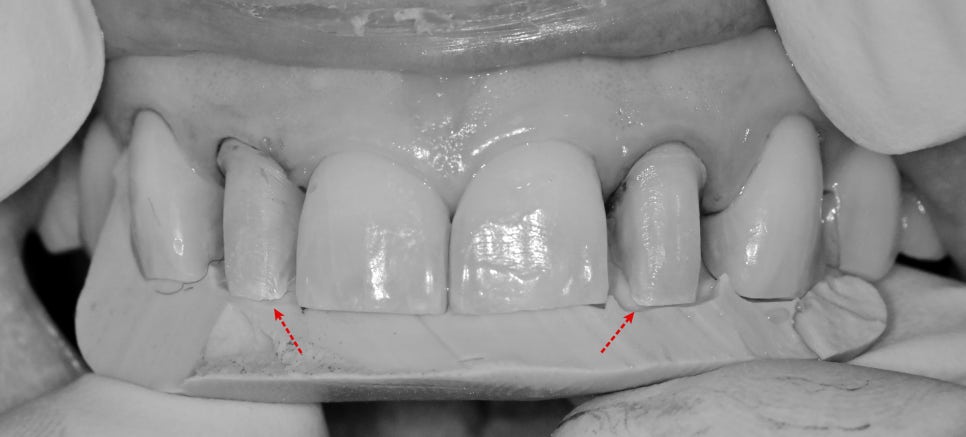

기존 라미네이트를 제거한 사진입니다.

제작될 라미네이트 예상 높이와 기존 치아의 높이가 같기 때문에

공간을 충분히 부여하지 못해 파절 위험성이 높아 보입니다.

최소한의 두께를 부여하기 위해 최소삭제를 하고

나머지 부위는 충분한 삭제가 이루어져 있어

삽입으로 정도만 수정하고 제작을 했습니다.